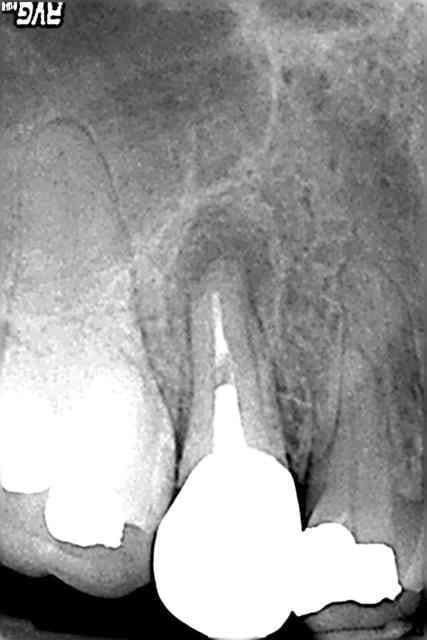

alors j'ai un patient reçu en consultation mi février pour douleur sur une 37 nécrosée.pas de douleur suite au traitement endo et jusqu'a ce jour.alors voila ma question au bout de combien de temp estimer vous que le processus de guerison est en route?et sur quels critères?donc en gros et ce qu'a la vue de la radio post op prise auourdhui je suis en mesure de proposer l'inlay core et la couronne a mon patient ou bien faut il encore attendre???

et oui l'endo est merdique je sais :(

Merdique ou pas y'a un signe de guerison a la radio, cf l'apex de la racine distale sur lequel l'os commence a revenir

Pour revenir à ton mouton, je trouve ton endo fort correcte, avec cependant un manque d'alésage compte-tenu qu'il s'agit d'une dent initialement infectée.

Mais vue la non-évolution de la lésion et la faisabilité de l'amélioration, je serais toi, je referais un alésage un peu + poussé, à la même longueur (si c'est celle donnée par ton localisateur d'apex, c'est la bonne :o) et SURTOUT beaucoup de javel, longtemps... au moins 15mn (les recommandations sont de l'ordre de 40mn d'après un article de l'ID mais bon...).